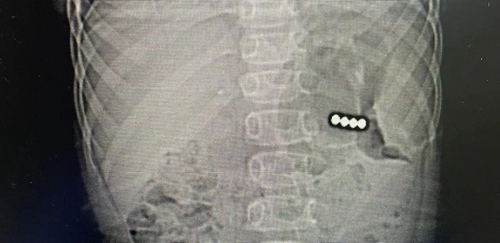

接診后,急診科立即開通異物救治綠色通道,為患兒完善相關(guān)檢查,并邀請(qǐng)消化內(nèi)科、小兒普外科專家共同會(huì)診。通過腹部CT、消化內(nèi)鏡探查,救治人員發(fā)現(xiàn)磁力珠停留在患兒胃部,已經(jīng)穿透胃壁,必須盡快手術(shù)。

小兒普外科團(tuán)隊(duì)立刻為洋洋進(jìn)行急癥手術(shù),4顆磁力珠全部取出,患兒已康復(fù)出院。